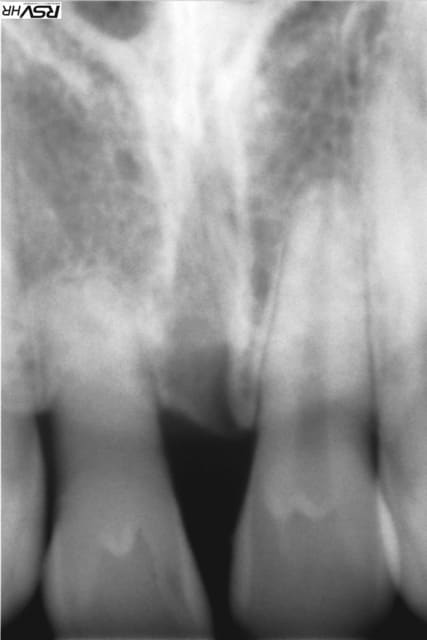

- 11 : extraction et implantation 11 rhyzalysée et mobile

- 21 : céramique pure sur 21.

Espaces mesio distaux : 8mm

Prévus implant Zimmer (finir les stocks) ou Legacy (j'en vois déja un venir...:) ) de 4,1 mm ou 4,2, longueur au moins 11,5 faisable

Wax-up fait (photos demain midi) : est prévu de fermer béance antérieure 11+21

Pas de recouvrement, occlusion inversée secteur 1/4, bout a bout incisif.